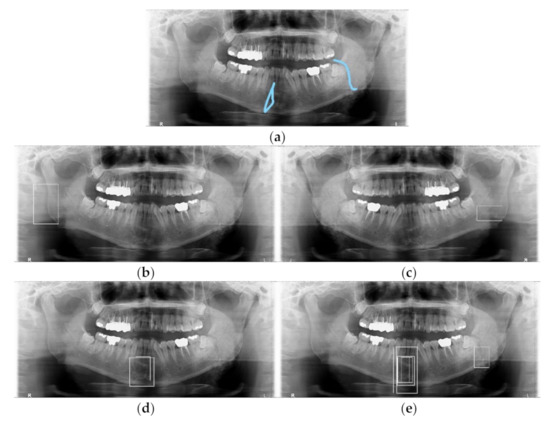

Mandibular fracture is one of the most frequent injuries in oral and maxillo-facial surgery. Radiologists diagnose mandibular fractures using panoramic radiography and cone-beam computed tomography (CBCT). Panoramic radiography is a conventional imaging modality, which is less complicated than CBCT. This paper proposes the [...] Read more.

Mandibular fracture is one of the most frequent injuries in oral and maxillo-facial surgery. Radiologists diagnose mandibular fractures using panoramic radiography and cone-beam computed tomography (CBCT). Panoramic radiography is a conventional imaging modality, which is less complicated than CBCT. This paper proposes the diagnosis method of mandibular fractures in a panoramic radiograph based on a deep learning system without the intervention of radiologists. The deep learning system used has a one-stage detection called you only look once (YOLO). To improve detection accuracy, panoramic radiographs as input images are augmented using gamma modulation, multi-bounding boxes, single-scale luminance adaptation transform, and multi-scale luminance adaptation transform methods. Our results showed better detection performance than the conventional method using YOLO-based deep learning. Hence, it will be helpful for radiologists to double-check the diagnosis of mandibular fractures. Full article

Show Figures